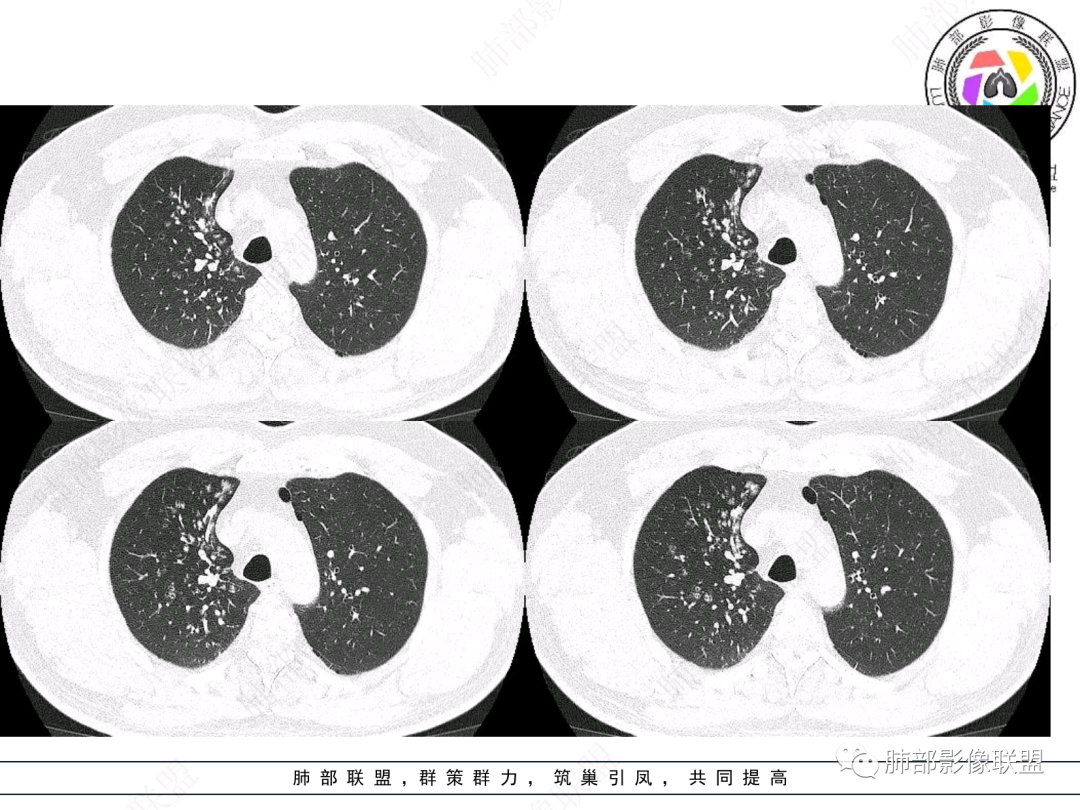

右肺上叶支气管截断,内见软组织密度结节,支气管管壁破坏,病变侵及管外,增强强化明显。右肺上叶沿气管血管束多发斑片影,考虑恶性性病变并阻塞性炎症,鳞癌,神经内分泌肿瘤。

右主支气管及肺门不规则软组织结节,点状钙化,不均匀强化,气管壁破坏,上叶支气管阻塞,分支粘液栓,血管束增粗,沿支气管分布多发结节,考虑鳞癌合并阻塞性炎症,鉴别结核。

右气管腔内结节,右肺门肿物,有钙化,右侧肺内多发气腔结节,散在,左肺部分支气管壁增厚,首先分析气管内结节,多考虑1鳞癌,形态规则,边缘光滑,宽基底,不太支持,远端阻塞性炎症不典型,2类癌,冰山一角和冰山分离了,不太支持3结核,多为支气管壁广泛增厚钙化,形成结节少,但是肺门肿块有钙化,可作为结核支持点,4黏痰,不像。其他不太懂了,肺内多发磨玻璃结节,并可见支气管手指状扩张,综合分析影像,考虑感染性病变,结核?有没有这样子的气管曲霉呢?向老师们学习。

男,52。间断咳嗽、咳痰2周,加重3天。胸部CT:右主、右上叶支气管多发软组织影,跳跃不连续,内可见小环状高密度,点状钙化,管壁破坏,上叶支气管堵塞,远端分支粘液栓,可见小支气管管壁增厚、管腔狭窄,沿支气管分布多发结节,无大片炎症不张。考虑:TB?NTM?鉴别Ca并阻塞性炎症。

患者中老年男性,咳嗽咳痰2周,无发热、咯血,伴胸闷、乏力及盗汗等,右上叶沿支气管血管束分布结节样变,管壁增厚;右肺门肿块,形态不规则、密度欠均匀,似有钙化,轻强化,主气道下端及右主支气管开口处见新生物,强化不支持类癌,镜下病变形态不大支持腺样囊性癌,考虑鳞癌可能性大,右肺上叶病变结核可能。

右肺上叶支气管开口见阻塞物影及强化,息肉样向腔内外浸润性生长,并有颗粒钙化,右肺上叶段支气管主干增粗及密度增高,见指套征,支气管血管旁见多发小斑点,小斑片影阻塞性炎性病灶〈小花小草表现〉,支气管镜示新生物血供丰富(结核完全排除),方向恶性,符合鳞癌特点,与小细胞Ca鉴定,临床专科支气管镜取材活检明确诊断。

腔内肿物,强化不均匀,强化程度为轻中度强化(CT值增加25HU),且强化特点为快进快出,右肺上叶支气管责任区域的阻塞性炎症加痰栓(气管镜也证实右上叶支气管内痰多)。这些均明确指向鳞癌。

一点不异常啊,分布在阻塞责任气管区域的支气管增粗伴腺泡结节(细支气管腔内及肺泡内阻塞性炎症伴痰栓),只不过还没有大片实变而已。@韩平     临沂市人民医院呼吸科

影像上分析的观察点:腔内、壁、腔外、远端,然后就是远端肺组织、淋巴结、肺血管、胸膜、其他肺部,这个人就是阻塞性炎症为主。